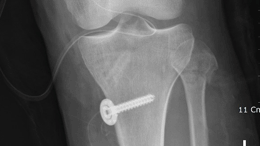

무릎인공관절치환술